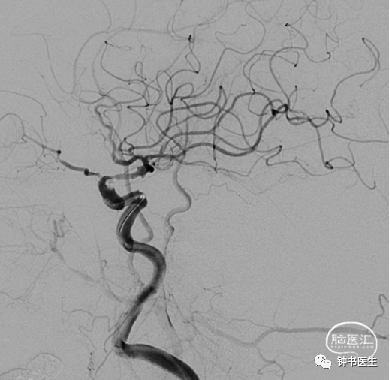

病例3

男,64岁

因“突发意识障碍2天” 入院

神志模糊,言语含糊,查体不配合,左侧肢体肌力3级。

Bp:131/66mmHg

既往:无特殊

2019-1-10 当地CT

2019-1-12 当地CT

神志模糊,烦躁,言语含糊,查体不配合,左侧肢体肌力3级。

2019-1-12

神经重症治疗思路

血压:90-100mmHg(入院131/66mmHg)

灌注压:60mmHg

脱水:双联

深度镇静镇痛(咪达唑仑+瑞芬)

ICP:15mmHg以内